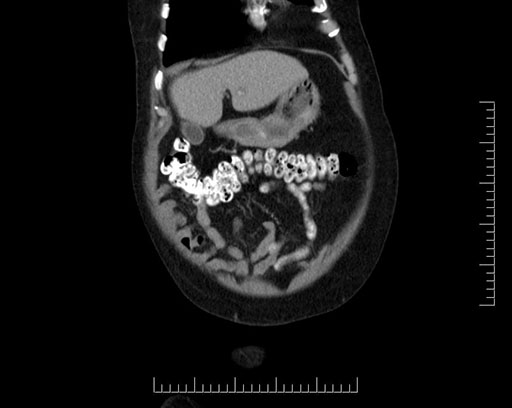

Coronal - stented